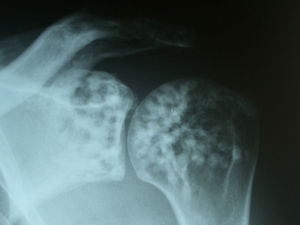

Diagnóstico y evoluciónEn la Rx que aportó la paciente se identificaron unos signos radiológicos que resultaron diagnósticos: numerosas imágenes radiopacas o esclerosas, pequeñas, homogéneas, bien definidas y circulares agrupadas en regiones periarticulares. Era un caso de osteopoiquilosis. No había manifestaciones clínicas con relación a esta enfermedad, tampoco se evidenciaron lesiones cutáneas. Se trataba de un hallazgo casual. A esta paciente se le solicitaron Rx de hombros, manos, pelvis, rodillas y pies (figs. 1–4), y se pudo comprobar que las lesiones halladas en el codo también estaban presentes en todas estas localizaciones. La osteopoiquilosis suele afectar a epífisis y metáfisis de huesos tubulares largos, carpo, tarso, pelvis y escápula de forma simétrica. El tamaño de las lesiones es uniforme.

DiscusiónLa osteopoiquilosis u osteopatía condensante diseminada es una displasia osteosclerótica asintomática. Su aparición antes de los 3 años es infrecuente, aparece tanto en varones como en mujeres. Existen casos hereditarios y esporádicos. Las manifestaciones clínicas suelen faltar, aunque en un 25% de casos pueden encontrarse lesiones cutáneas que consisten en infiltraciones fibrocolágenas, predisposición a la formación de queloides y lesiones similares a las de la esclerodermia. Los hallazgos radiológicos son diagnósticos1. El diagnóstico diferencial debe hacerse con metástasis osteoblásticas, mastocitosis y esclerosis tuberosa2. La distribución simétrica, la afectación de epífisis y metáfisis, y el tamaño uniforme de las lesiones son datos sugestivos de osteopoiquilosis. El aspecto normal de una gammagrafía ósea acabaría de apoyar el diagnóstico.